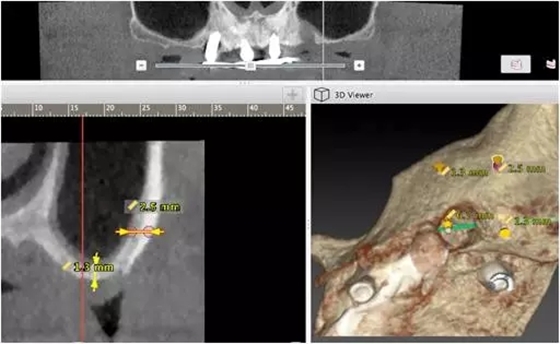

10個(gè)月后出現(xiàn)左上頜咬合痛,X線檢查發(fā)現(xiàn)上頜左側(cè)前磨牙區(qū)傾斜種植體周圍低密度影,臨床檢查種植體松動(dòng),其余種植體骨結(jié)合良好,遂拔除該種植體(圖3-4)。愈合3個(gè)月,CBCT片顯示:25區(qū)種植窩空虛(圖5),愈合不佳,26區(qū)竇底剩余骨高度不足2mm(圖6),其余種植體骨愈合良好,15區(qū)傾斜種植體邊緣骨疑似吸收至第三螺紋(結(jié)合全景片)?;颊咭蠊潭ㄐ迯?fù)。